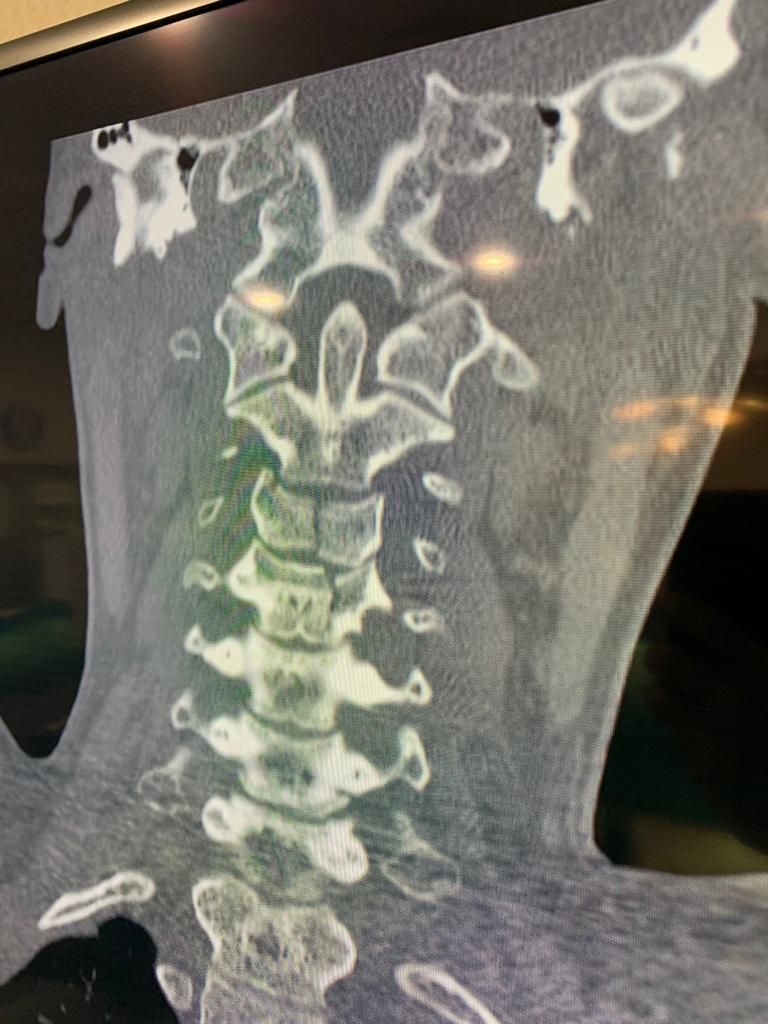

- Cirugía de columna cervical

- Cirugía de columna lumbar

Cirugía de hernia discal cervical

Cirugía de la estenosis raquídea

Microcirugía de hernia de disco